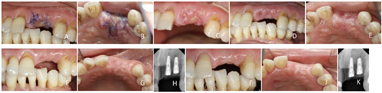

临床检查:21残根状,断面见龋坏,位于龈下约1.0 mm,叩诊(-),牙周探诊深度≤3 mm,牙无松动,牙龈无红肿,龈沟内未见异常分泌物。11牙龈缘退缩约2 mm,11牙龈缘高度同11,采用探针透照法,即牙周探针探入龈沟内时探针外形不可见,判断牙龈生物型为厚龈型[3,4,5]。恒牙列,22缺失,牙槽嵴顶黏膜凹陷,牙龈未见红肿、破溃等不适;15、16、17、36、37缺失,缺牙区牙槽嵴顶黏膜平坦。11、12、13、14、23、24、25、33、34、35、44、45唇侧颈部见"V"形缺损,牙本质暴露,探诊、冷诊敏感。双侧下颌后牙舌面见牙石覆盖牙面颈部约1/3,牙龈红肿,探诊出血,31、41松动Ⅱ度,口内余留牙牙周探诊深度1~3 mm,下前牙附着丧失3~4 mm。开口度、开口型正常,颞下颌关节、黏膜、颌面部均未见异常(图1)。

X线影像学检查:锥形束CT显示21牙根长度约10 mm,唇侧皮质骨板完整、连续,厚度约1.0 mm,根尖区未见异常,可用牙槽骨宽度8.2 mm、高度23.8 mm;22可用牙槽骨宽度5.9 mm、高度18.1 mm,21、22缺牙间隙距离15.4 mm(图2)。